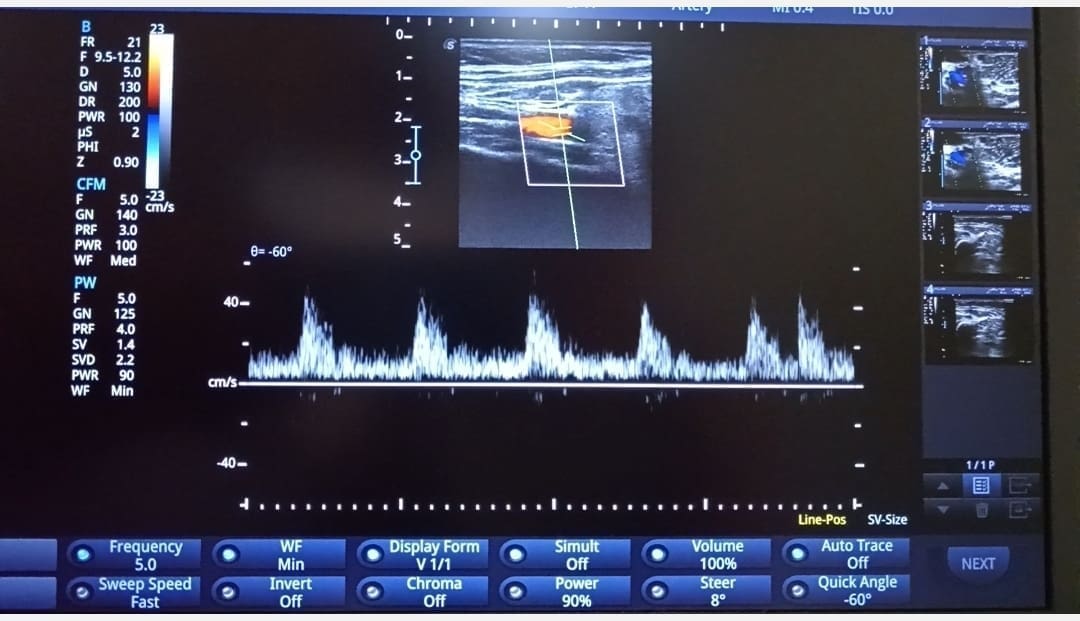

Color Doppler

Color Doppler je suvremena ultrazvučna pretraga kojom se mjeri brzina i smjer protoka krvi u određenoj krvnoj žili.

- Color Doppler arterija je pretraga koja omogućuje točnu anatomsku i funkcionalnu promjenu na suženoj ili začepljenoj arteriji.

- Color Doppler vena je pretraga koja omogućuje dijagnostiku proširenih vena te otkrivanje ugruška (tromba)unutar površnih i dubokih vena uz procjenu protoka krvi u venama.